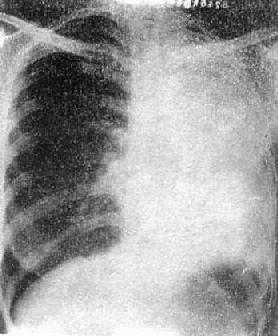

(1)一侧性肺不张:X线现为患侧肺野均匀致密,纵隔向患侧移位,肋间隙变窄(图3-1-7)。健侧肺可有代偿性肺气肿。

图3-1-7 一侧性肺不张

左侧支气管阻塞引起左侧全肺不张,显示左侧肺野均匀致密,

纵隔向患侧移位,肋间隙变窄,膈升高